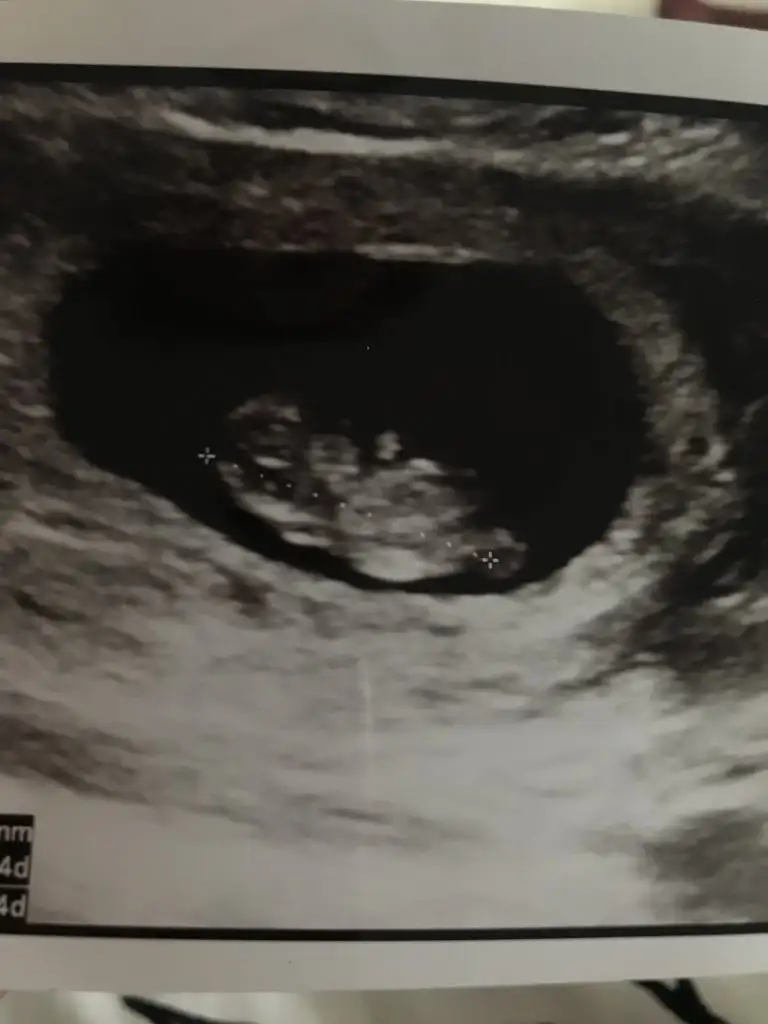

Kağıdının diğer kısmında yazıyor olabilir sağ altta yazıyor geneldeEki Görüntüle 2295859

Kızlarr biz geldikkher sey yolunda çok şükür 8 haftayla uyumlu dedi doktor. Ama doktor çok sevimsizdi ya agzından gramla laf aldık. Bu kağıtta bebeğin boyu nerede yazıyor ben bulamadım da. Geriden gelme olayi düzelmis sanirim doktor 8 hafta dedigine göre